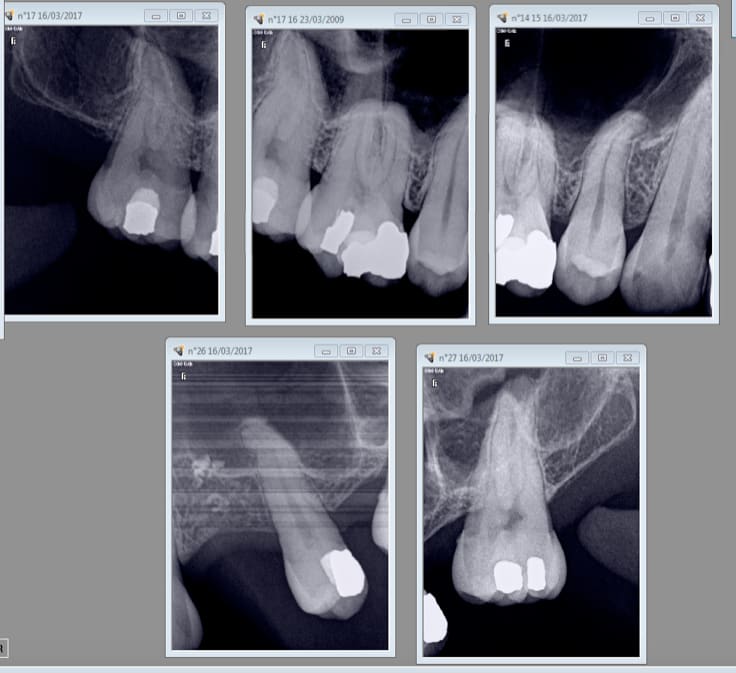

Celui ci bien complet.-)

Signe d'appel la petite souris est passée pour la 11. -)

Pourquoi elle , il y en a d'autres qui frétillaient de la queue ;o)